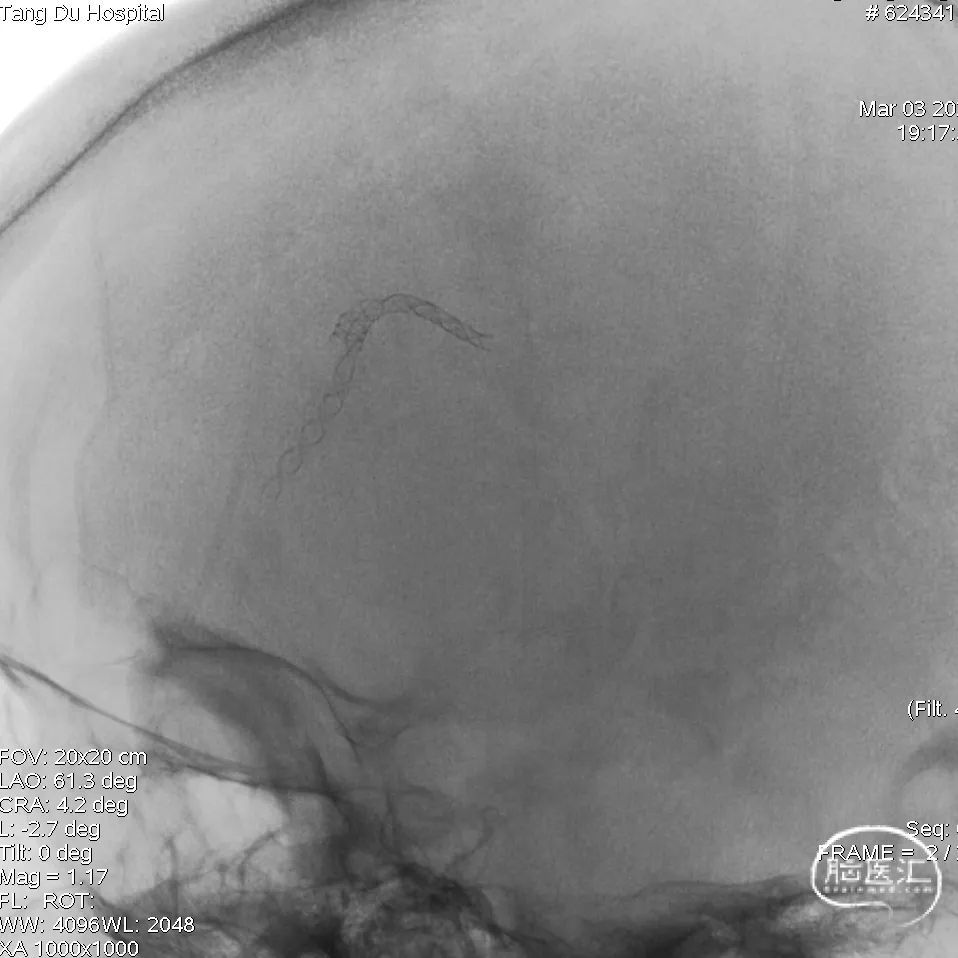

将血流导向密网支架经微导管同轴通过动脉瘤,缓慢撤微导管释放血流导向密网支架,全程放完后,再次造影确定支架内血流通畅。

再次行全脑血管造影,见血流灌注良好、通畅,退出导管。

术后正侧位造影显示支架贴壁良好,血管重塑满意,血流改善明显。